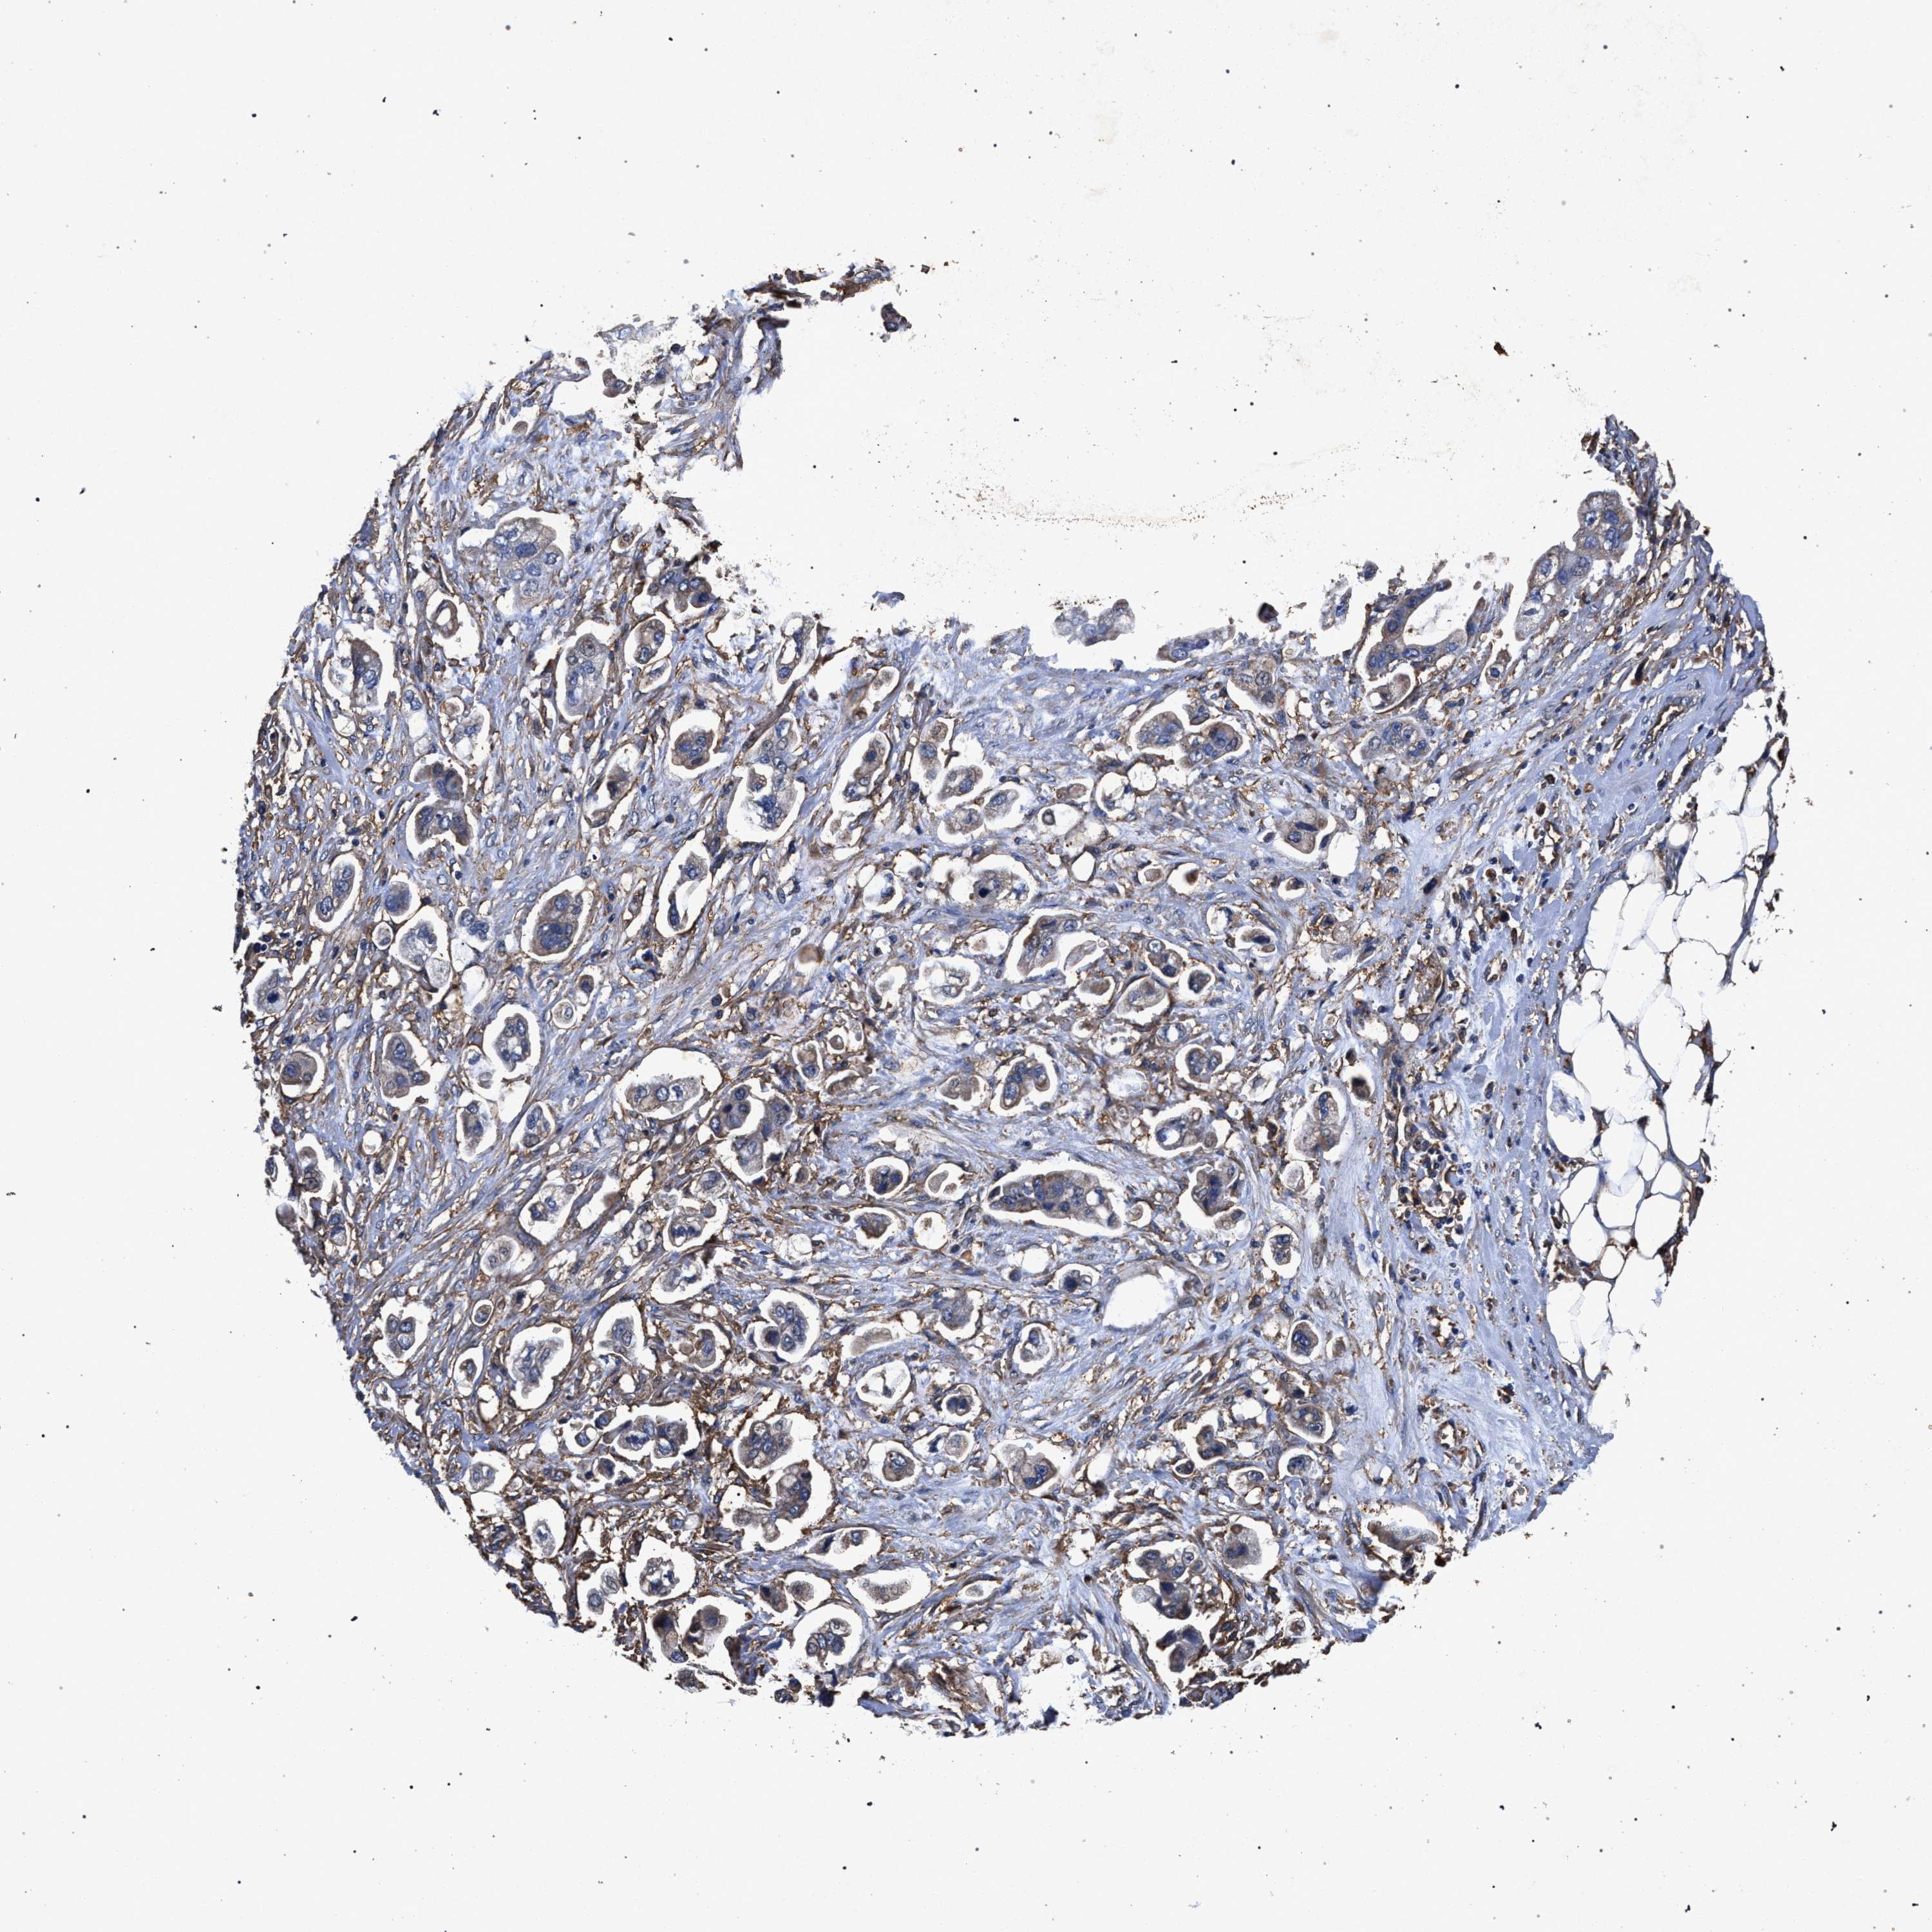

STOMACH CANCER - Protein expressioni

A mouse-over function shows sample information and annotation data. Click on an image to view it in a full screen mode. Samples can be filtered based on level of antibody staining by selecting one or several of the following categories: high, medium, low and not detected. The assay and annotation is described here.

Note that samples used for immunohistochemistry by the Human Protein Atlas do not correspond to samples in the TCGA dataset.

Antibody stainingi

Antibody staining in the annotated cell types in the current human tissue is reported as not detected, low, medium, or high, based on conventional immunohistochemistry profiling in selected tissues. This score is based on the combination of the staining intensity and fraction of stained cells.

Each image is clickable and will lead to virtual microscopy that enables deeper exploration of all samples and also displays staining intensity scores, fraction scores and subcellular localization as well as patient and tissue information for each sample.

Antibody HPA067595

Antibody HPA069443

Antibody CAB022062

Staining

High

Medium

Low

Not detected

Intensity

Strong

Moderate

Weak

Negative

Quantity

>75%

75%-25%

<25%

None

Location

Nuclear

Cytoplasmic/membranous

Cytoplasmic/membranous,nuclear

Adenocarcinoma, NOS

Adenocarcinoma, High grade